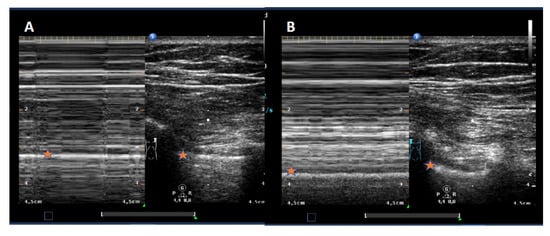

No specific thorax preset was used. The TUS examination was done by one experienced ultrasound examiner as described earlier [7]: it started parasternal at the adjacent intercostal spaces (ICR) at the medio clavicular line (MCL). Pleural integrity was assumed if all three following features were detectable: pleural sliding, B-Lines, and lung pulse (M-Modus). In the absence of one out of these items, the lung point, as the proof of pneumothorax, was searched for following the ICR laterally and marked with a strip placed on the skin. If a unilateral lung point was not detectable, a total pneumothorax was assumed. Absence of lung sliding was documented by addition of M-mode with the typical barcode-sign [7], as shown in Figure 1.

Figure 1. TUS with M-Modus showing the absence of lung sliding (A, “barcode sign” with pneumothorax) and presence of lung sliding (B, “seashore-sign”, no pneumothorax). The difference could be noted in the M-Modus-parts below the star-marked white line, that reflects a regular (B) or missing sliding pleural line, leading to repetitive horizontal lines in the case of a pneumothorax in part (A).